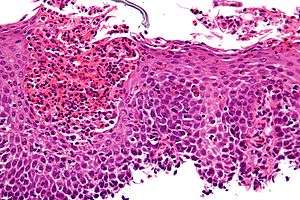

Micrograph showing eosinophilic esophagitis. H&E stain. | |

Endoscopically, ridges, furrows, or rings may be seen in the esophageal wall. Sometimes, multiple rings may occur in the esophagus, leading to the term "corrugated esophagus" or "feline esophagus" due to similarity of the rings to the cat esophagus. Presence of white exudates in esophagus is also suggestive of the diagnosis.[6] On biopsy taken at the time of endoscopy, numerous eosinophils can be seen in the superficial epithelium. A minimum of 15 eosinophils per high-power field are required to make the diagnosis. Eosinophilic inflammation is not limited to the esophagus alone, and does extend through the whole gastrointestinal tract. Profoundly degranulated eosinophils may also be present, as may microabcesses and an expansion of the basal layer.[1][4]